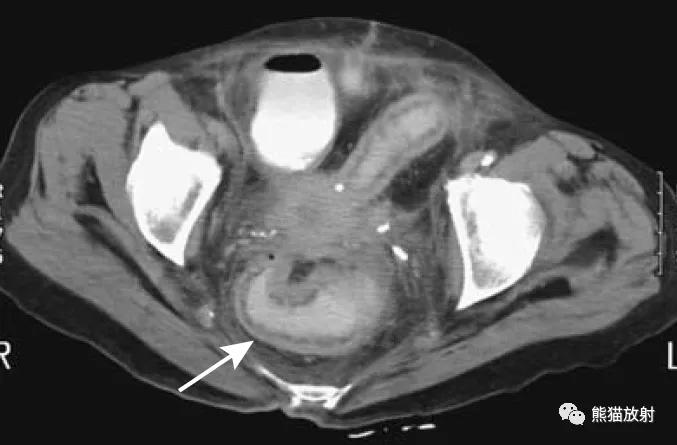

直肠周围脓肿(易误诊为直肠癌)。4个月前因增生行前列腺切除术,出现便秘。盆腔CT显示直肠病变并管腔变窄(箭头)。T1和T2加权图像显示直肠壁增厚和周围充满液体的结构(箭),提示脓肿或坏死性肿瘤。